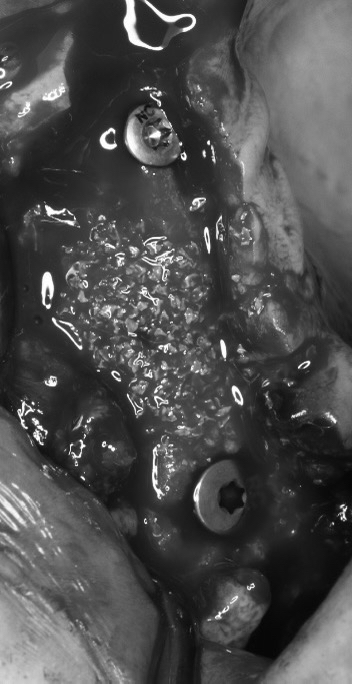

该患者就是因牙周病导致牙齿松动脱落,我们通过在半口牙槽骨上植入8颗种植体,然后在种植体上安装连桥牙冠,从而恢复半口牙齿的咀嚼功能和美观。相对于传统的种植修复方式缺一颗种一颗。4-8颗种植体的种植手术创伤相对较小,大大的减少了患者的疼痛感。